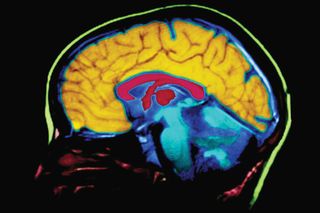

Sepideh Shokouhi, PhD, assistant professor of psychiatry and behavioral sciences at Vanderbilt University Medical Center, and colleagues looked at how tau protein — a toxic protein that causes brain cell death when clumped together and is commonly associated with cognitive decline in Alzheimer’s — spreads differently in the brains of men and women. They compared PET scans of healthy people to those with mild cognitive impairment by mapping the brain as a network of tau-connected regions. The research found that women with cognitive impairment had the highest density of tau networks along with higher overall tau burden. The study also found healthy women had several key regions in the brain that served as hubs connecting other, different regions of the brain, which could accelerate the brain-wide spread of tau in women. “The differences that we observed indicate the strong possibility that there are sex differences in the structural and functional connections in the brain, which may contribute to women’s increased risk for Alzheimer’s,” Shokouhi said at the conference, as reported in a press release.

To investigate the reason behind this, Erin Sundermann, PhD, a neuropsychologist at the University of California, San Diego, School of Medicine, and colleagues from other institutions, compared the brain’s ability to metabolize glucose — a primary energy source for the brain and a measure of brain function — between 569 men and 453 women at different stages of Alzheimer’s. The research showed that women in the initial stages of Alzheimer’s showed higher levels of glucose metabolism than men, suggesting that women compensate for Alzheimer-related brain changes by increased brain metabolic function; this, researchers say, may contribute to the advantage they have in verbal memory tests in the disease’s early stages.